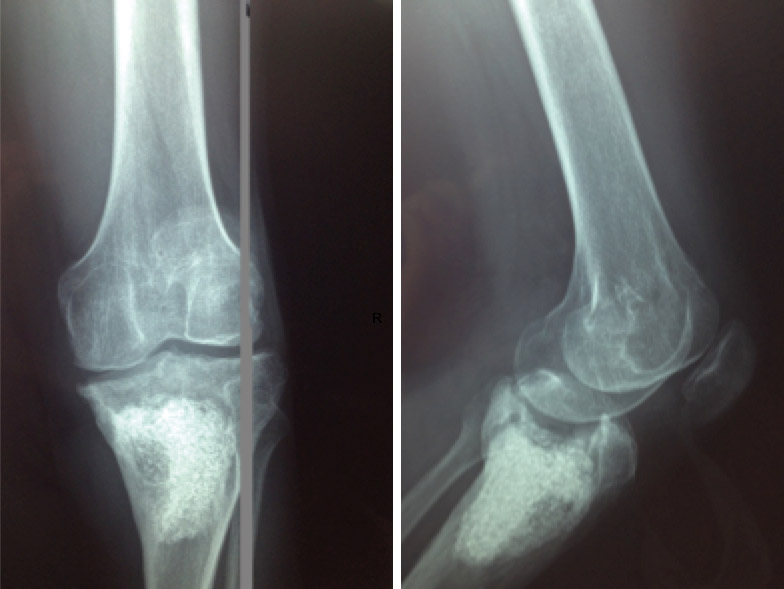

La evolución fue favorable, mejorando la clínica y los parámetros analíticos, resolviéndose la infección y consiguiendo una extensión de –5° y flexión de 95°, aunque persiste un defecto óseo epifisometafisario proximal en tibia izquierda, como se observa tanto en la radiografía como en la TC que se le realizaron tras un año de evolución, donde además se aprecia una artrosis femorotibial incipiente (Figuras 2 y 3).